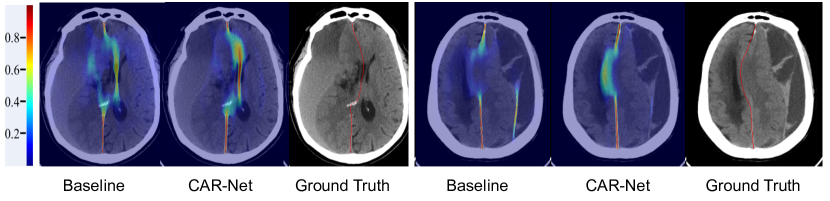

We replace the CAR-Net with plain U-Net in our pipeline as the baseline model. In order to obtain more contextual features, we attach a context-aware refine module based on the feature pyramid generated by the U-Net. For verifying the effectiveness of the CAR-Net, we perform ablation study on proposed CAR-Net under two loss conditions, one is training with CRL and the other is training without CRL. As shown in the last four rows of Table. 2, under both loss conditions, we observe that CAR-Net yields better performance consistently in four evaluation metrics on both datasets, compared to the baseline model. As shown in Fig. 2, the segmentation probability map of midline generated by the CAR-Net is more accurate, especially in shifted parts of largely deformed midline. The quantitative and qualitative results demonstrate that our proposed CAR-Net can obtain more contextual features, which can predict the largely deformed midline better.

Refer to caption

Figure 2: Qualitative comparison results of segmentation probability maps between the baselinhttps://www.overleaf.com/project/5e4120603cca900001191c74e model and proposed CAR-Net.

3.0.4 Effect of Connectivity Regular Loss.

To verify the effectiveness of the proposed CRL, we conduct experiments with the baseline model and CAR-Net. It could be observed from the last four rows of Table. 2 that employing CRL achieves better performance compared to the model without CRL supervision, especially in the MSDE and HD metric, which indicates the proposed CRL can reduce the error of maximum shift significantly. Furthermore, in the inference stage, the CRL of the predicted midline can also serve as a connectivity indicator to verify the performance gain of the structural connectivity. As shown in Table. 1, the connectivity indicator of the model with CRL is far smaller than counterpart without CRL. In summary, the proposed CRL can improve not only the distance performance of the midline delineation but also the midline structural connectivity effectively. Some qualitative comparisons are shown in Fig. 3, which further demonstrated the effectiveness of the CRL.

Figure 3: Qualitative comparison between the CAR-Net with or without CRL.